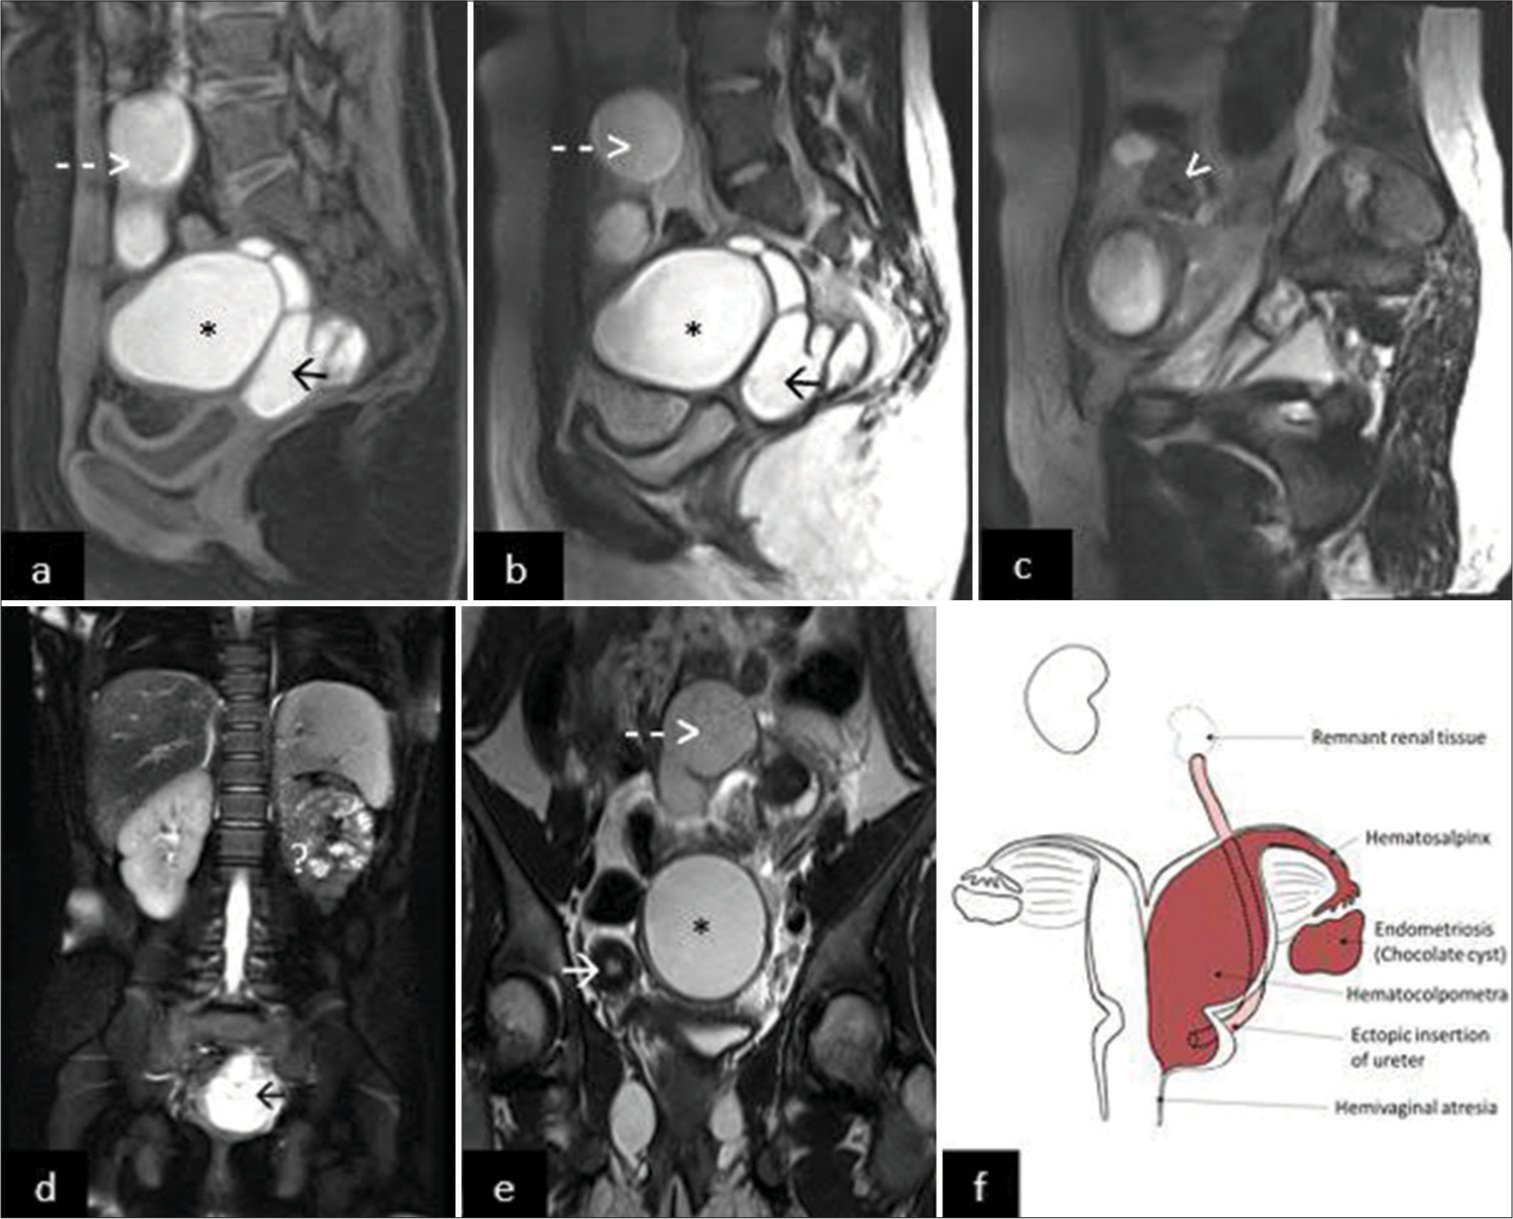

Contrast-enhanced MRI of the pelvis and upper abdomen revealed two uterine cavities and cervices, suggesting didelphys uterus [Figure 1]. The right horn of the uterus [Video 1, AR2], right cervix [Video 1, AR9], and right ovary [Video 1, AR1] appear normal. The left horn of the uterus and left cervix were significantly dilated with hemorrhagic contents within, suggestive of hematometra [Video 1, AR3] and hematocolpos [Video 1, AR4], [Figure 1]. A dilated tortuous tubular structure was seen adjacent to the left ovary with hemorrhagic contents within, suggestive of hematosalpinx [Video 1, AR5]. A cystic lesion showing T2 shadowing was seen in the left ovary, suggestive of a chocolate cyst [Video 1, AR6], with normal peripherally arranged follicles noted [Video 1, AR7], [Figure 1].

- An 11-year-old girl presented with pain in lower abdomen since the onset of menarche 8 months back. (a) T1-weighted sagittal images showing hematocolpometra (*), hematosalpinx (dashed arrow), and hematomegaureter in pouch of Douglas (black arrow); (b) T2-weighted (T2w) sagittal images showing hematocolpometra (*), hematosalpinx (dashed arrow), and hematomegaureter in pouch of Douglas (black arrow); (c) T2w sagittal images showing chocolate cyst (white arrowhead) with peripherally arranged follicles; (d) T2 fat-saturated images showing empty left renal fossa (?) with dilated hematomegaureter in the pelvis (black arrow); (e) T2w coronal images showing uterus didelphys with normal right horn (white arrow) with hematocolpometra (*) and hematosalpinx (dashed arrow); (f) A simplified diagram showing didelphys uterus with left hematocolpometra, hematosalpinx, and endometriotic chocolate cyst in the left adnexa. Left blind hematomegaureter with distal insertion into the cervix. Obstructed hemi vagina with transverse septum. The left kidney is not identified in the renal fossa, with atrophic remnant renal tissue at the blind end of the ureter in the left hemipelvis. The right horn of the uterus, right cervix, and right ovary is normal. Normal morphology solitary right kidney was noted.

Normal morphology solitary right kidney was seen. The left kidney could not be identified in the renal fossa [Figure 1]. There was a dilated, tortuous tubular structure in the midline in the pouch of douglas [Video 1, AR10], [Figure 1d] with a proximal blind end in the left para vertebral region [Video 1, AR8], up to the level of L4–L5 vertebrae and distal ectopic insertion into the cervix [Video 1, AR11], showing hemorrhagic contents within due to backflow from the hematocolpos, suggestive of blind ectopic hematomegaureter. Atrophic renal tissue was noted at its blind end in the left hemi pelvis. Vagina was compressed due to the aforementioned dilated structures, and it was difficult to comment on the presence of a septum; however, obstructed hemi vagina due to a transverse septum was suspected.